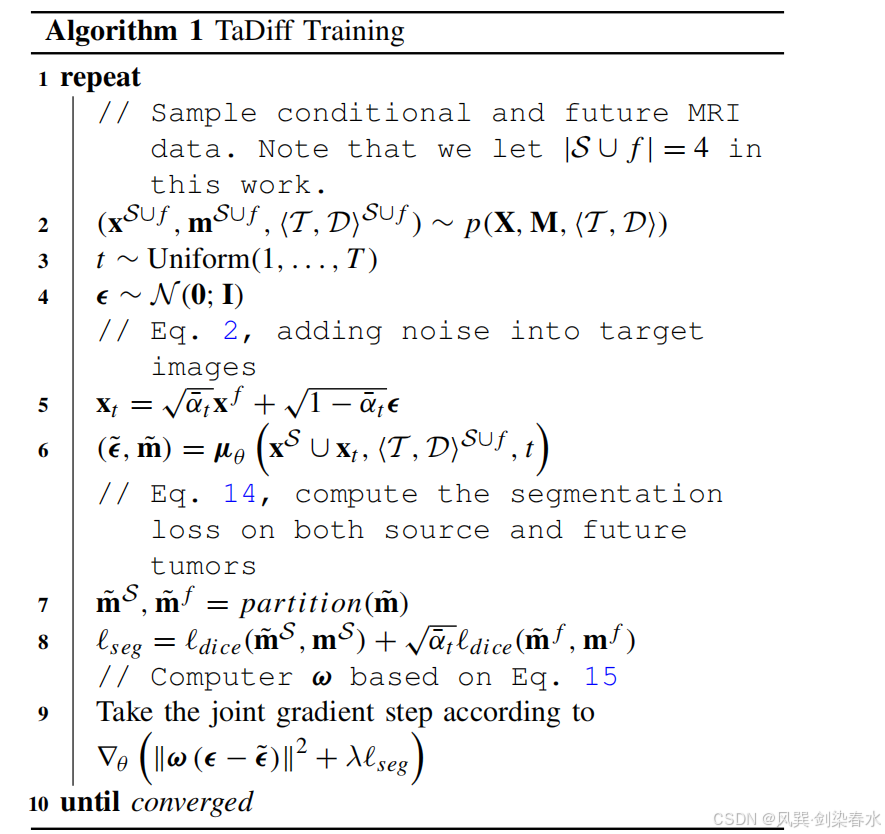

因此,TaDiff 模型不仅仅是一个纯粹的扩散模型,而是一个结合了去噪扩散和分割任务的混合网络,能够以端到端的方式生成未来的 MRI 图像并同时分割出肿瘤的纵向生长掩模。算法1 和 算法2 介绍了 DDPM 训练和采样过程。

需要注意的是,扩散分支和分割分支共享编码器组件。扩散过程需要 600 步来生成目标图像,而分割过程仅利用最后 10 步。这些最后的步骤提供了质量最高的输入,本文生成 10 个 mask。随后对这些 mask 进行加权平均,以生成最终的分割 mask。这种方法确保分割 mask 能够从扩散过程后期阶段产生的高质量输入中获益。

3.3、联合损失

由于该模型不仅预测了源图像和未来 MRI 中的肿瘤掩模,还包含了常规扩散噪声。因此,在分割子任务中采用了 dice 损失,其定义为:

其中 ∣ ⋅ ∣ |·| ∣⋅∣ 表示 L 1 L_1 L1 范数。由于在高时间点 t t t 时, x t x_t xt 中的信息不足,模型无法从图像中准确预测出合适的掩码。因此,根据 x t x_t xt 中 x 0 x_0 x0 的权重来调整未来分割的 Dice 损失。最终,分割损失被定义为:

第一个 dice 损失用于源图像的分割( m ~ s \widetilde m^s m s),而第二个 dice 损失则根据噪声水平因子 α ˉ \bar α αˉ 进行缩放或加权,该因子用于预测噪声目标图像( x t x_t xt)的肿瘤掩模( m ~ f \widetilde m^f m f)。

最后,用于训练 TaDiff 模型的联合损失函数被定义为:

其中 λ λ λ 参数用于控制联合优化训练过程中分割损失的大小。基于实验和观察结果,本研究中将 λ λ λ 设为 0.01。